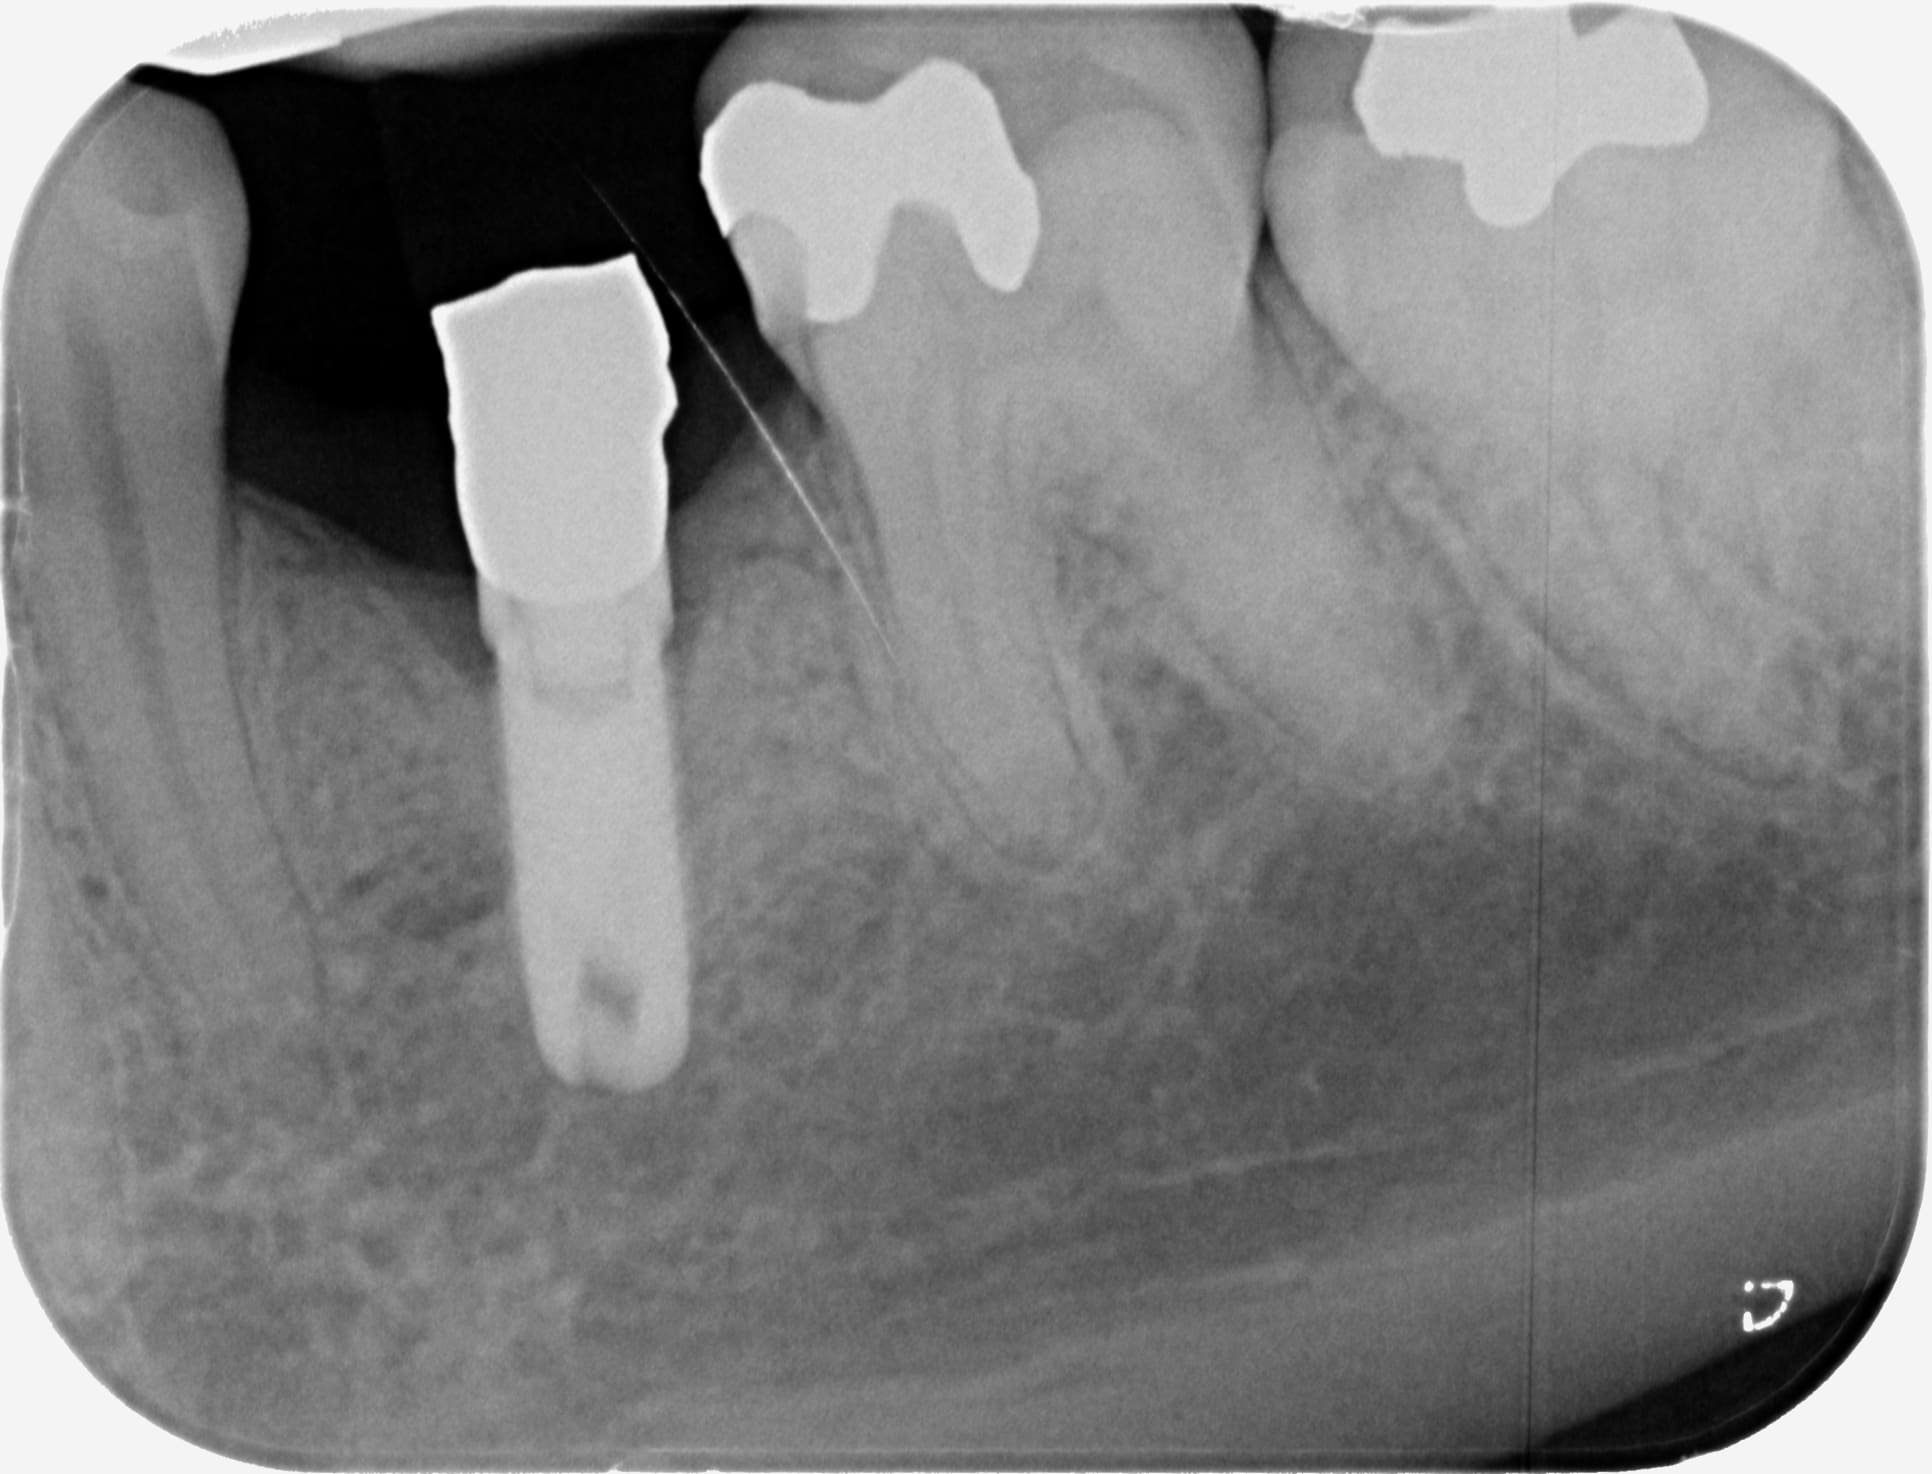

Bonjour à tous, qui peut me dire de quelle marque sont les différents implants de cette radio ?

Merci par avance !!

pas de rétros pas d'identification possible

j'ai que ça... peut être un peu flou et pas sur que ça aide...

première radio: Sterioss